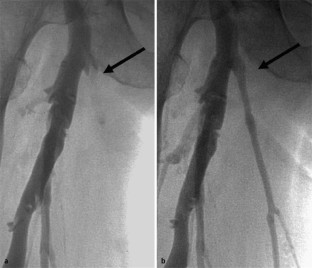

Abb. 1

Abb. 2